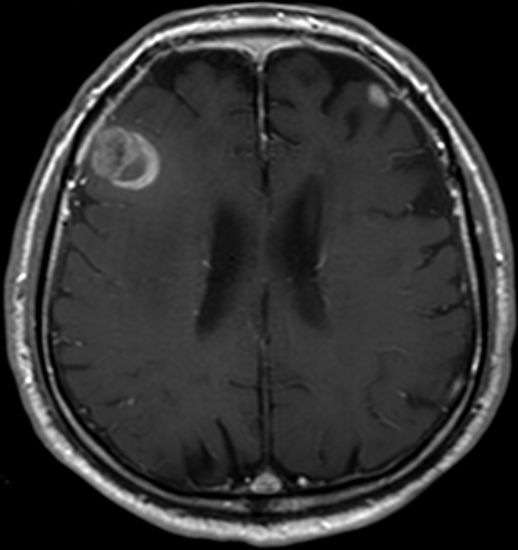

| Hirnmetastasen | OS 6,7 Monate nach Ganzhirnbestrahlung oder oder stereotaktischer Bestrahlung

![]() | |||